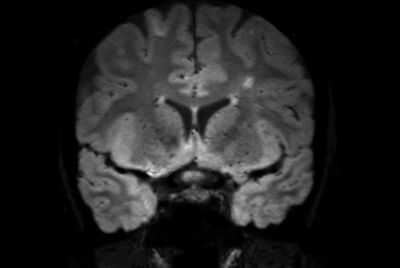

Alzheimer’s Disease Anti-Amyloid Immunotherapies (ARIA) 1.5T